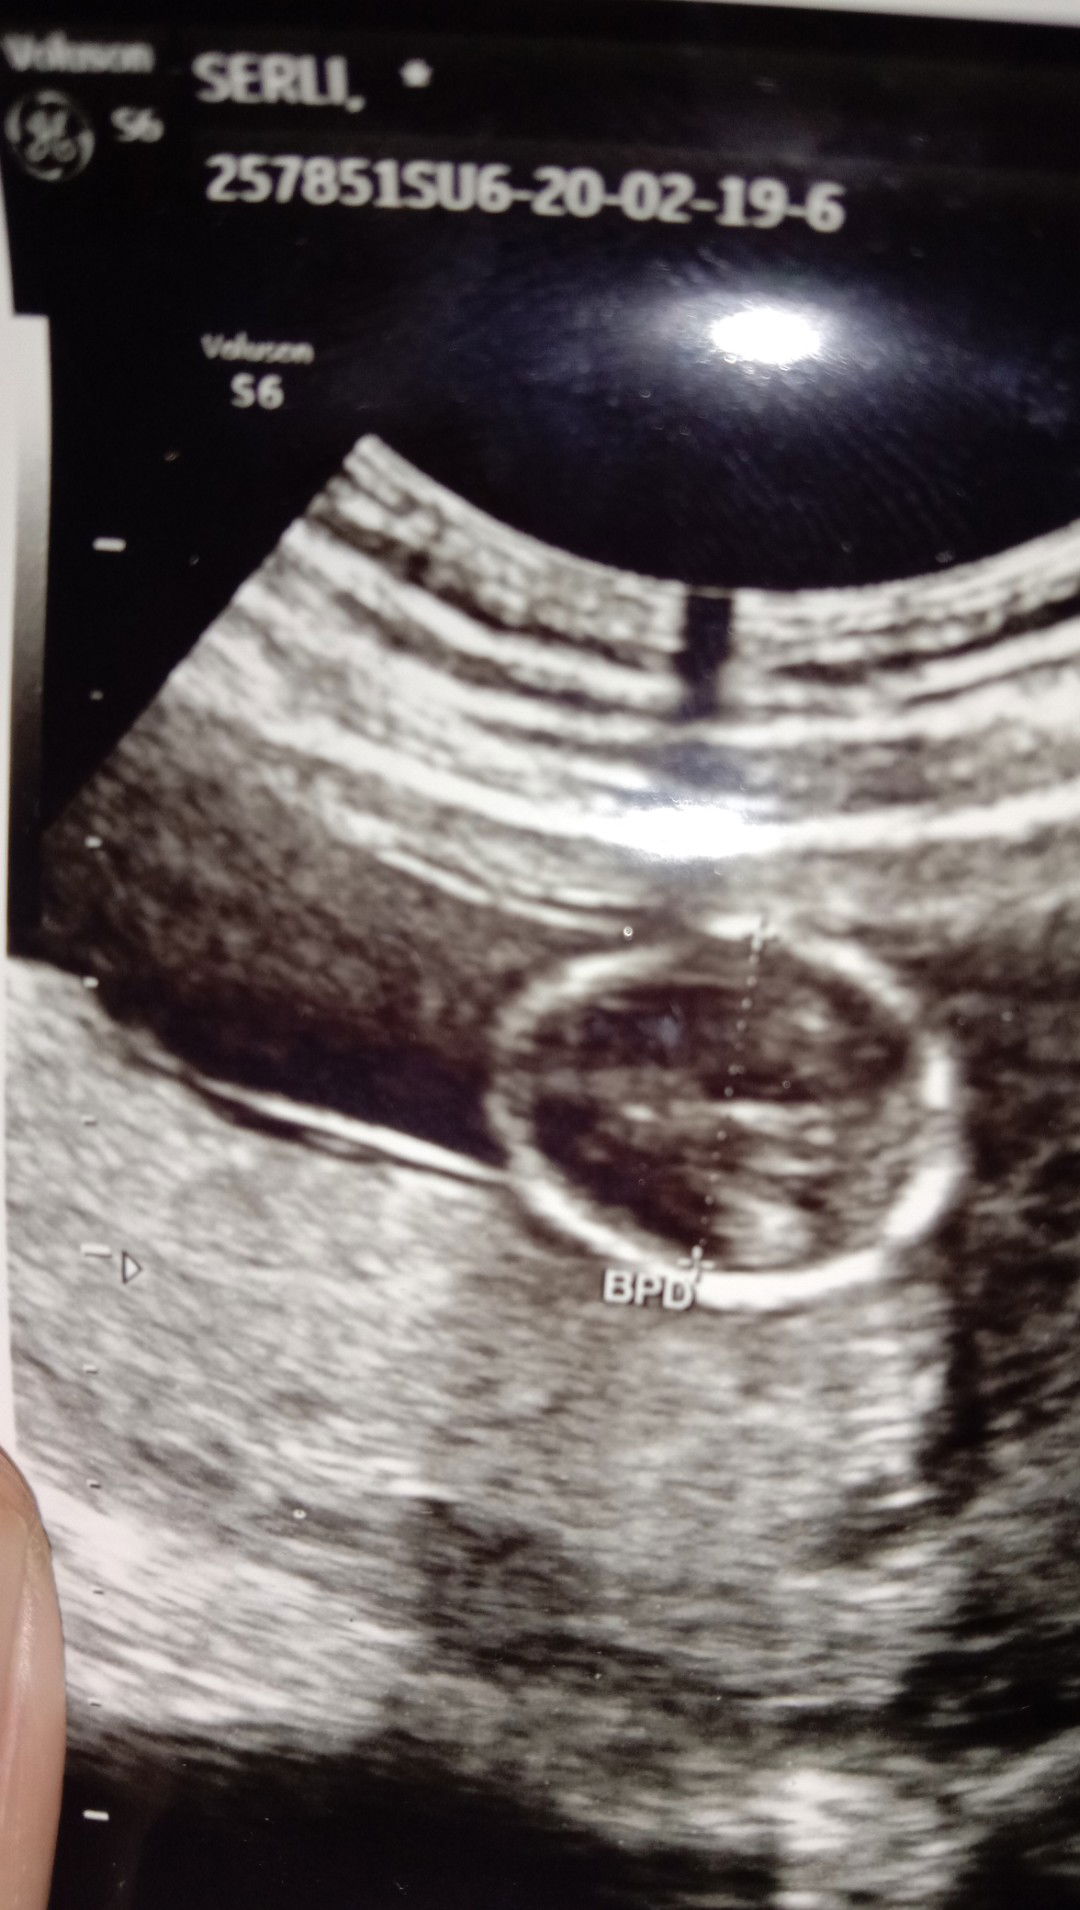

usg

Halo bunda, saya beberapa waktu lalu periksa kehamilan mandiri, hasilnya 2 garis yg satunya masih samar, beberapa waktu kemudian saya memutuskan memeriksa ulang dgn cara yg sama, & hasilnya sudah positif, barulah saya bawa ke dokter, setelah saya usg, ternyata hasil komputer menunjukan bahwa saya sudah hamil 14w2d, tp perkiraan saya barulah sekitar 2 bulan atau lebih! Apakah hasil usg selalu akurat? & apakah yg usg nya 14w-d janinnya segini atau lebih besar ya? Saya membandingkan dgn yg lain, dr post disini, rata2 janinnya & kantung nya sudah besar, tp kata dokter kehamilan saya baik, & air ketubannya cukup, walaupun anak kedua, ttp saya masih kurang berpengalaman.. Siapa tau ada yg bisa berbagi pengetahuan?

Ukuran di usg itu berdasarkan besar/berat janin bun Kalo uk dr hpht bs beda sm dr usg